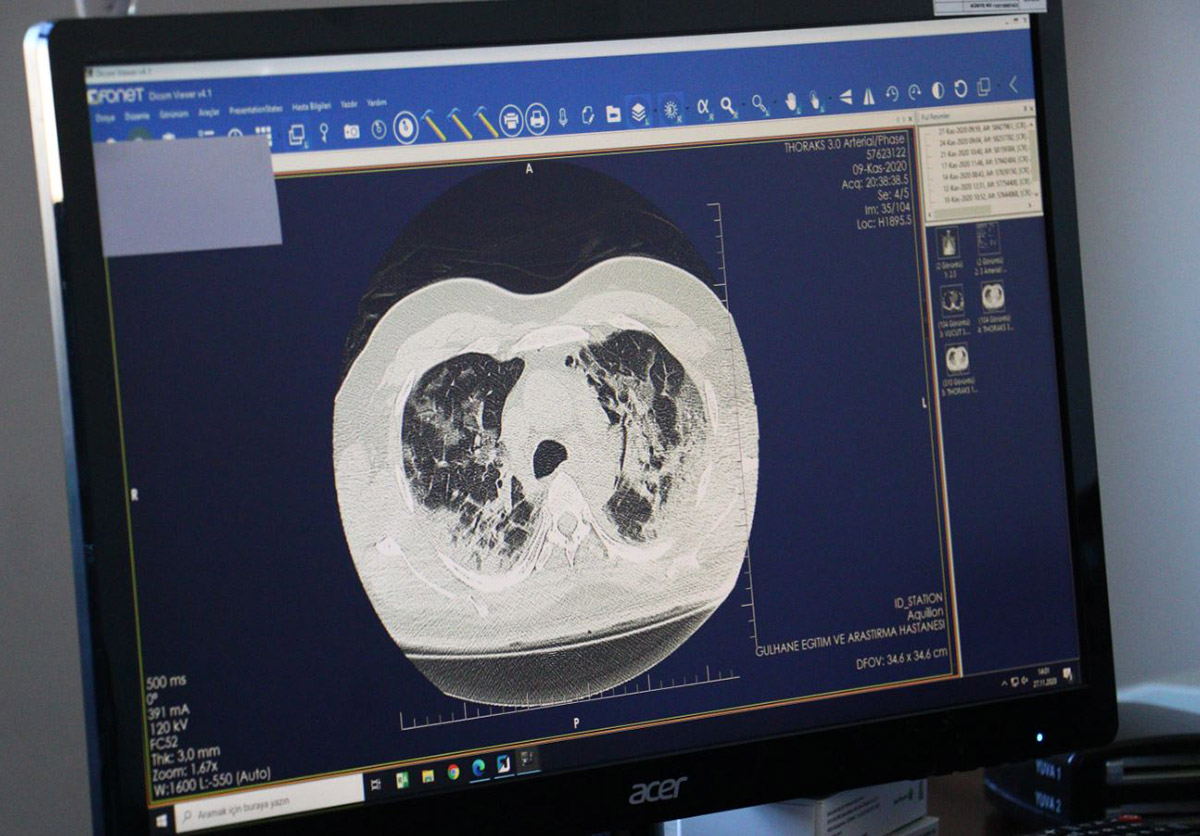

KORONAVİRÜSÜN AKCİĞERDEKİ HASARI TOMOGRAFİDE

Ankara Şehir Hastanesi Yoğun Bakım Uzmanı ve Bilim Kurulu üyesi Doç. Dr. Sema Turan, koronavirüsün akciğerde yarattığı tahribata dikkat çekerek, "Virüsün şiddeti devam ediyor. Yarattığı akciğer hasarı inanılmaz" diyerek sözlerine şöyle devam etti:

"Bir yoğun bakım hekimi olarak söyleyebilirim ki gördüğümüz akciğer filmleri ve tomografileri olayın şiddetinin oldukça fazla olduğunu ve bu hasta gruplarının da zannedildiği gibi çok ileri yaş olmadığını; yaşamı içerisinde aktif yaşamını devam ettiren bireylerin de çok ağır klinik tablolarla bize başvurduğunu söylemek zorundayım. Hastanın akciğer tomografileri ve filmlerini gördüğünüz zaman 'Bu hastalar acaba nasıl nefes alabiliyor?' diyebileceğiniz görüntüler. Bizim halkımızdan tek beklentimiz kurallara uysunlar ve yoğun bakıma ihtiyaç duyulmasın; yoğun bakım ortamı gerçekten zor bir ortam, hastalar için de çok sıkıntılı bir yer. Kendilerinin buna ihtiyaç duymamaları için kısıtlamalara uyulmasını tavsiye ediyorum" diye konuştu.